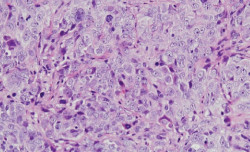

Una investigación, liderada por la investigadora del Centro de Investigación del Cáncer (Universidad de Salamanca-CSIC), del Instituto de Investigación Biomédica de Salamanca (IBSAL), y del CIBER de Cáncer, Azucena Esparís-Ogando, ha identificado que la activación anormal de la proteína WNK1 afecta drásticamente a la supervivencia de las pacientes con cáncer de ovario y permite evaluar la eficacia preclínica de nuevas terapias para tratar esta enfermedad.

El componente bacteriano del microbioma --comunidad de microorganismos que también consta de virus, levaduras y hongos-- es un importante indicador para la detección precoz, el diagnóstico y el pronóstico del cáncer de ovario, según un nuevo estudio del Centro de Medicina Individualizada de Mayo Clinic (Estados Unidos) publicado en `Scientific Reports`.

Expertos en Obstetricia y Ginecología del Hospital Materno-Infantil Quirónsalud Sevilla han destacado este miércoles, con motivo del Día Mundial del Cáncer de Ovario, que solo un 25 por ciento de los casos se detecta en etapa inicial.